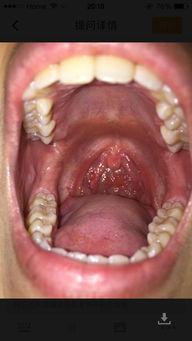

虽然黑皮瓜有很多好处,但是有些人吃黑皮瓜后会出现喉咙疼的情况。这究竟是怎么回事呢?

1. 过敏反应:有些人对黑皮瓜中的某些成分过敏,如黑皮瓜中的某些蛋白质或糖分。过敏反应可能导致喉咙发痒、疼痛,甚至出现水肿等症状。